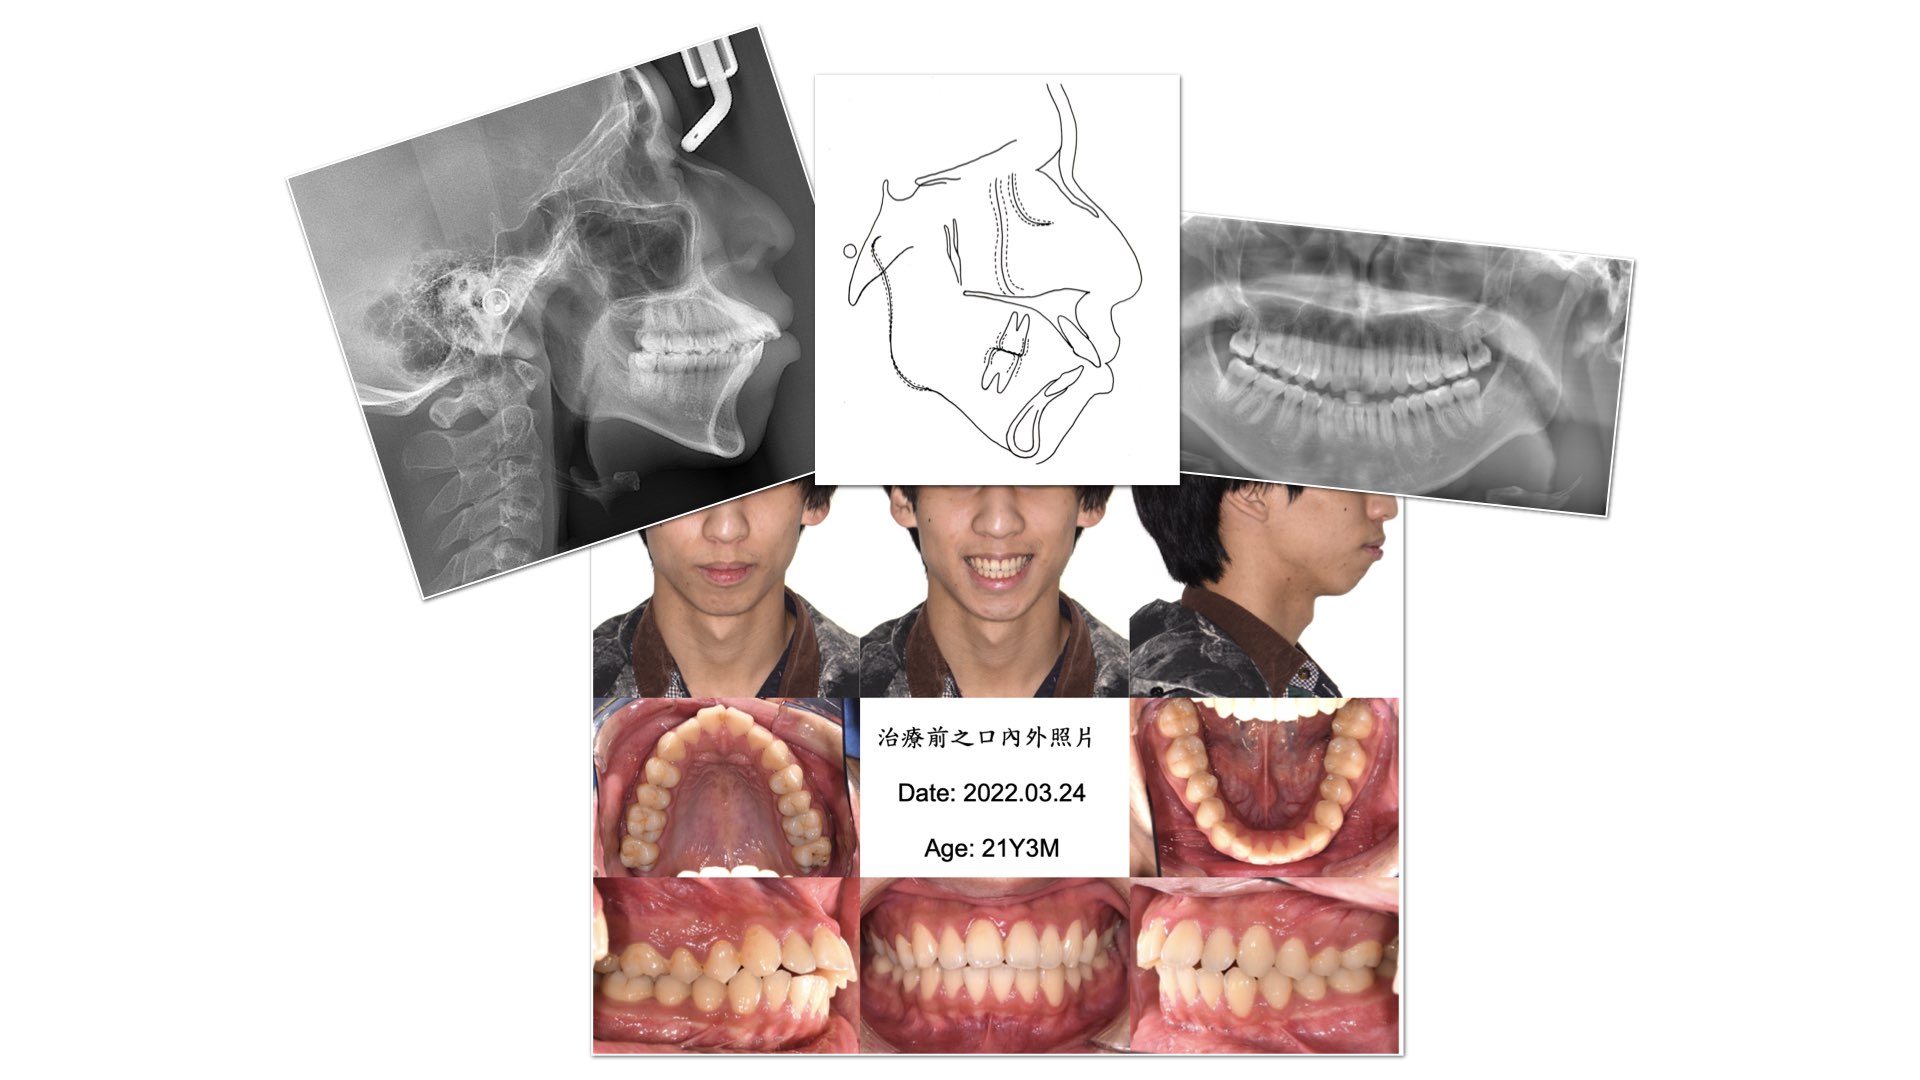

在正式開始矯正之前,會先進行完整紀錄:包含全口X光、側顱X光、口內掃描或取模,以掌握您目前的牙齒排列與咬合狀況,同時也會與您討論希望透過矯正改善的重點與期望目標。